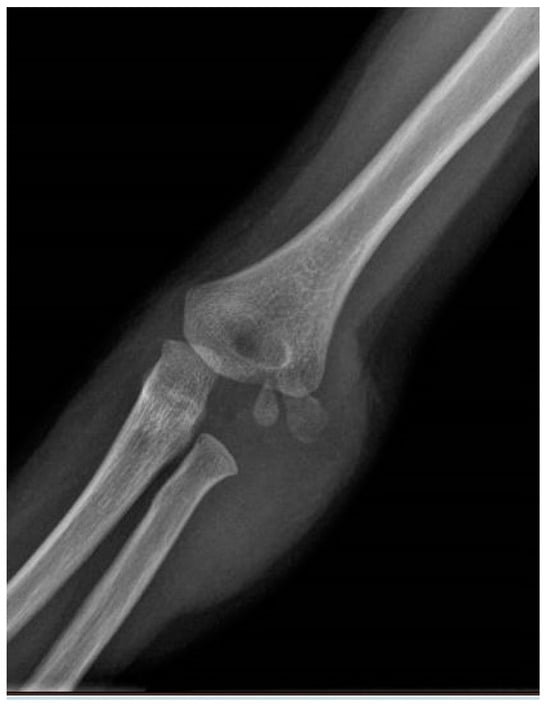

| Carrying Angle | 12.3° | 4.28 | 5–22° |

| Contralateral Carrying Angle | 12.3° | 3.87 | 5.9–20° |

| Baumann Angle | 78.9° | 13.5 | 60.4–112° |

| Contralateral Baumann Angle | 79.1° | 12.7 | 63–118.8° |